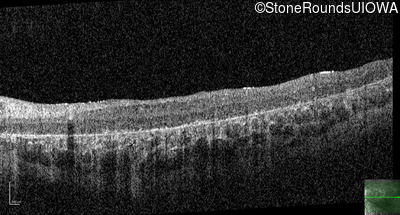

Age at visit: 8 years

This 8 year old girl had normal vision until age 6 when she failed a school vision screening. That year, she was able to play softball well, but this year she often loses sight of the ball and is often hit by it.